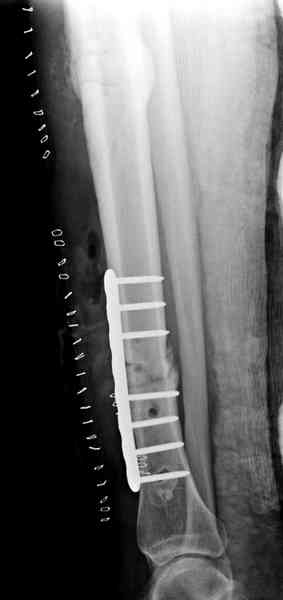

"При его рассмотрении с рентгенологом и морфологом сошлись, что это не фиброзная дисплазия, что было первым предположением по рентгенограммам. В полости было и мягкотканое образование. Окончательно заключение дадут через несколько дней"

По локализации и по характреру опухоли мало напоминает остеобластому, может, представленные биопсийные материалы адамантиномы помогут вашим морфологам дифференцировать опухоль (Basiloid cells, pseudoglandular pattern and peripheral palisading)

Недавно на нашей ежемесячной Morbidity&Mortality

conference мы разбирали похожий случай, ложный сустав большеберцовой кости после резекции опухоли.

К нашему онкологу-ортопеду обратился больной с жалобами на боли в голени, из рассказа - год назад была сделана биопсия большеберцовой кости, но название заболевания "не запомнил”.

Оперирован в военном госпитале с заменой сегмента

аллокостью большеберцовой кости и после демобилизации явился для постоянного наблюдения по месту жительства.

В литературе "A Classic Adamantinoma Arising from

Osteofibrous Displasialike Adamantinoma in the Lower Leg: A case report and Review of the Literature похожие снимки.

Наши имели проблему со сращением, пришлось им сделать динамизацию, дополнительную аутопластику.

Снимки представлены.